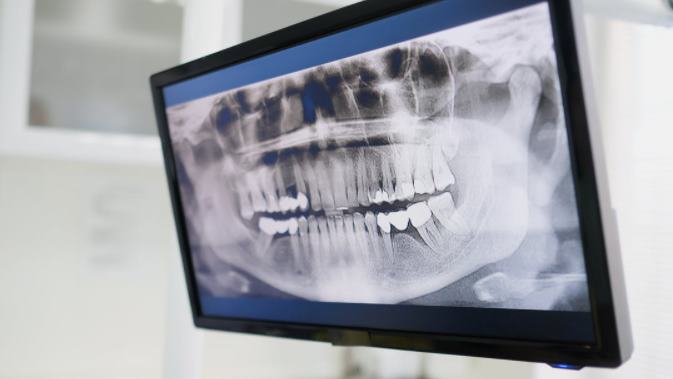

Стоматологи используют цифровые изображения зубов и десен ( рентген), чтобы определить, в чем заключается проблема. С помощью этих изображений они могут диагностировать проблему и составить план лечения. Однако иногда обычного рентгена становится недостаточно.

Сегодняшнее рентгеновское оборудование значительно улучшилось, и другие методы визуализации, такие как МРТ (магнитно-резонансная томография), также нашли свое применение в стоматологии. Эти методы обеспечивают детальную визуализацию мягких тканей, таких как мышцы, соединительная и нервная ткани, хрящевые структуры.

Цифровая визуализация все больше заменяет традиционные изображения в стоматологическом лечении. Решающими преимуществами этих систем являются более быстрая диагностика, меньшее количество повторений, и прежде всего, снижение облучения пациента до 90% благодаря более низкой дозе облучения.

Цифровая визуализация в основном используется в стоматологии для диагностики заболеваний и контроля их течения. Перед лечением заболеваний пародонта, резекцией верхушки корня, установкой зубного протеза или хирургическим удалением зубов мудрости следует сделать цифровой рентген.

Рентгеновские лучи используются для получения цифровых изображений, проникая в ткани, кости и зубы, попадая на пластины изображения или специальные датчики. Электронная пластина сохраняет отпечаток до восьми часов, после чего изображение создается на специальном устройстве. В сенсорной модели изображение считывается непосредственно в программу рентгеновским аппаратом, к нему можно получить мгновенный доступ с компьютера.